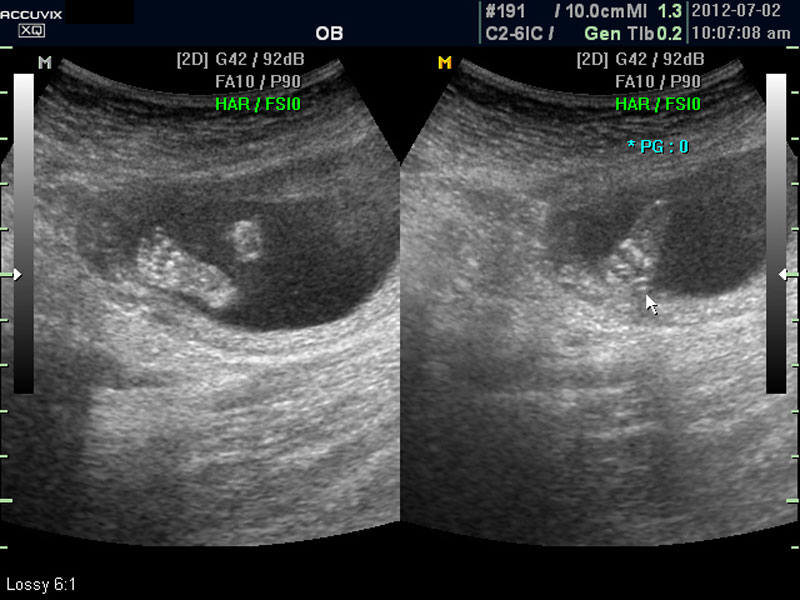

위 사진은 태아의 발바닥 사진인데 사진에서 보는 것처럼 그러나 이 시기는 손가락이나 발가락 또는  심장 내부의 구성 이상 등의 세세한 부분은 아직 크기가 작아서 제대로 확인하기 어려운 시기입니다.

따라서 부분 부분 살펴 보면서 해당 모습을 찍어서 저장하거나 인쇄하여 드리기도 하는 것이며 아래 사진은 태아의 다리 부분을 찍은 것입니다.

양수의 양은 태아의 건강과 관련된 지표로 너무 많거나 너무 적으면 좋지 않은데 그 절대양을 측정할 수는 없어서 양수가 많은 부분의 깊이를 측정하거나 혹은 개략적으로 전체에서 차지하는 부분을 봐서 이상 여부를 판단합니다.

사진에서 검게 보이는 것이 양수입니다. 양수에 대하여는 색깔이나 밀도 등 다른 요소는 알기 어려워서 그 양만 가지고 판단을 하게 됩니다.

임신 초기나 중기의 양수 이상 중에는  대체로 태아의 건강 이상으로 인한 양소 과소증이 더 많은 편입니다.